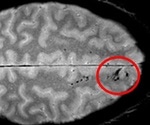

Study shows microbleeds after head injury signal danger to brain function